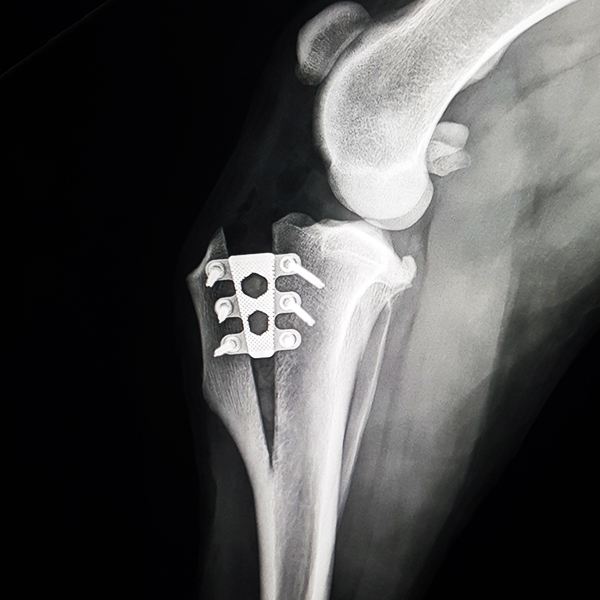

CrCL Ruptures in Small Breeds:

Osteotomies or extra capsular repair

CrCL Ruptures in Small Breeds: Should we use osteotomies instead of extra capsular repair?

TTA RAPID®

Learn how to perform CCL Repair with TTA RAPID®

Tiny TTA RAPID®

Learn how to fix CCL Ruptures in Tiny Animals with the Tiny TTA RAPID® System

Rapid Luxation

Learn how to fix Patella Luxation with the RAPID LUXATION System

Patella Luxations can be challenging, especially using previous techniques. Luckily, we have developed a seamless, simple technique for addressing both patella luxations and cruciate ligament ruptures.